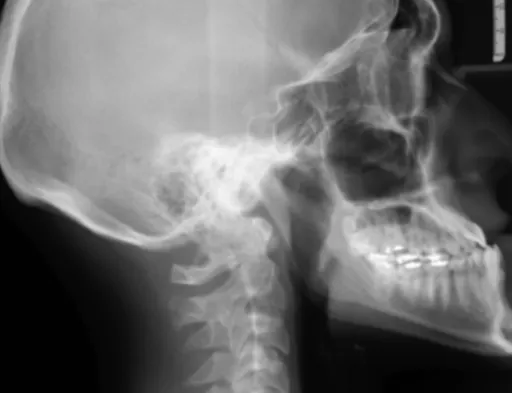

병원에 도착하면 의료진은 신속하게 환자의 상태를 평가하고, 뇌졸중 여부를 진단하기 위한 검사를 시행합니다. CT, MRI 등의 영상 검사를 통해 뇌혈관의 상태를 확인하고, 뇌졸중의 유형과 발생 위치를 파악합니다. 뇌졸중으로 진단되면 즉시 치료를 시작합니다. 뇌경색의 경우 혈전 용해제를 투여하여 막힌 혈관을 뚫어주고, 뇌출혈의 경우 출혈을 멈추게 하는 치료를 시행합니다. 뇌졸중 치료는 환자의 상태와 뇌졸중의 유형에 따라 다르게 진행되며, 의료진의 지시에 따라 적절한 치료를 받는 것이 중요합니다.